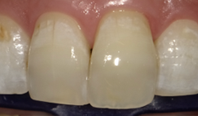

治療後(アフター)